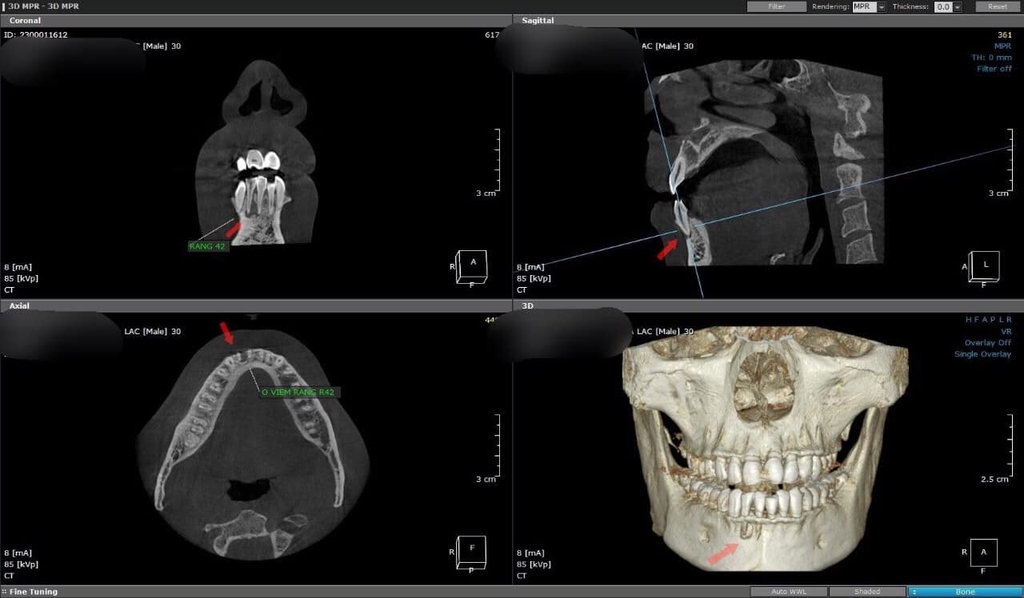

Việc ứng dụng CBCT trong chẩn đoán trước phẫu thuật giúp các bác sĩ nha khoa đánh giá toàn diện cấu trúc giải phẫu vùng hàm mặt, từ đó lên kế hoạch điều trị chính xác và an toàn. Nhờ hình ảnh 3D, các bác sĩ có thể xác định rõ vị trí, kích thước và mối quan hệ giữa các cấu trúc giải phẫu quan trọng như dây thần kinh, xoang hàm, rễ răng... trước khi tiến hành phẫu thuật. Nhờ CBCT, bác sĩ có thể tránh tổn thương dây thần kinh, giảm thiểu nguy cơ tê môi dưới sau phẫu thuật.

Đối với các ca phẫu thuật vùng răng sau, CBCT giúp đánh giá chính xác kích thước và hình dạng của hố dưới hàm, từ đó xác định vị trí đặt implant an toàn và hiệu quả. Đặc biệt, trong trường hợp có lẹm xương, CBCT giúp phát hiện sớm và lên kế hoạch phẫu thuật phù hợp, tránh nguy cơ thủng xương và chảy máu.

Với các ca phẫu thuật vùng răng trên, CBCT giúp xác định chính xác vị trí và kích thước của xoang hàm, lỗ khẩu cái, hố trong vòm họng... Nhờ đó, bác sĩ có thể lên kế hoạch nâng xoang, mở vạt hoặc các thủ thuật phẫu thuật khác một cách an toàn và hiệu quả.

Ngoài ra, CBCT còn được ứng dụng để đánh giá chất lượng xương, phát hiện các bệnh lý về xương hàm, lập kế hoạch ghép xương... Nhờ đó, bác sĩ có thể đưa ra những quyết định điều trị tối ưu cho từng bệnh nhân.